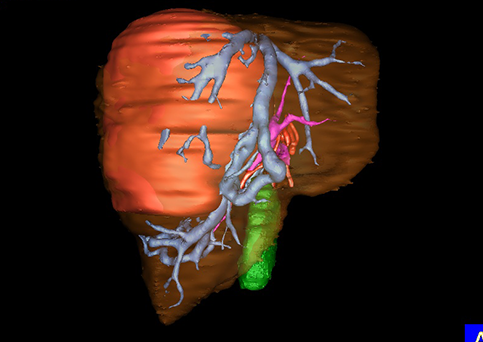

近年来由于数字医学的发展,基于可视化三维重建技术的计算机辅助手术系统极大推进了小儿肝脏肿瘤的精准手术的进步。可以立体透视肝脏解剖、精确掌握肝段的边界、精确测算肝段乃至任意血管所支配的功能体积、准确定位病灶及其与邻近血管的解剖关系,最终对不同手术方案进行比较、筛选和优化。因此,计算机辅助手术规划系统是实现精准肝切除的有力辅助工具,是未来数字外科、精准外科等21世纪外科新理念的重要技术支撑。

计算机辅助手术规划系统具有良好的操作可行性、计算准确性和三维显示效果,可半透明、交互式显示真实的肝内立体解剖关系和空间管道变异,准确计算肝内管道的直径、走行角度,两点间的垂直距离,和任意血管的支配或引流范围等传统二维影像无法获取的信息,有助于实施个体化手术,提高了手术的确定性、预见性和可控性。计算机辅助手术规划系统可直观显示预留肝脏的结构和功能,并可通过虚拟切割功能辅助术者对手术方案进行蹄选和优化,系统评估手术风险和制定对策,改变了部分二维规划的术式和切除范围,使部分二维规划认为不能切除的患者成功手术,提高了手术的根治性、安全性和病变的可切除性,更加符合精准肝脏外科的术前规划要求。详见第11章。

随着计算机技术及影像检查技术的不断发展,以精确的术前影像学和功能评估、精细的手术操作为核心的精准肝切除技术日益受到重视。基于数字医学的计算机辅助手术技术(computer-assisted surgery,CAS)则是实现肝脏精准手术操作的基础。计算机辅助手术系统(CAS)可将术前二维(two dimensional,2D)的CT/MRI影像数据进行三维(three dimensional,3D)重建,建立个体化的肝脏三维解剖模型,清晰显示肝脏内脉管系统的走行及解剖关系,还原病灶与其周围脉管结构的立体解剖构象,准确地对病变进行定位、定性和评估,制定合理、定量的手术方案,实施个体化的肝脏血管取舍分配方案及实施精准肝脏手术。一般认为CAS包括:创建虚拟的患者的图像;患者图像的分析与深度处理;诊断、手术前规划、手术步骤的模拟;术中实时导航。应用本技术后,由于可以更清晰地看出肿瘤的界限,特别是根据肝血管的显影,判断出肿瘤与门静脉及肝静脉的关系以在手术前较准确地估计出手术成功切除的可行性。以往部分根据普通强化CT判断无法手术的病例而被评估为可以成功切除并手术成功。

图23:肝中叶肿瘤二维CT图像